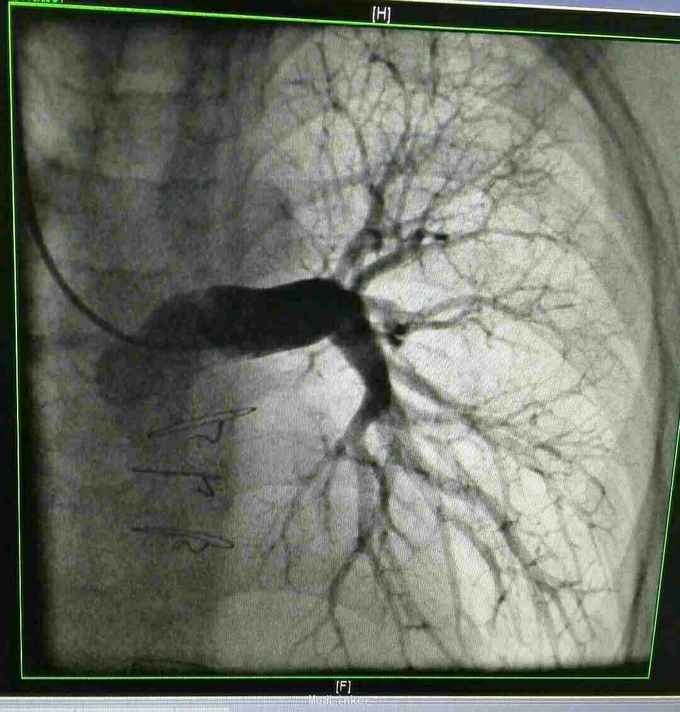

诊断 先天性心脏病 双向Glenn术后 单心室 大动脉转位 肺动脉瓣重度狭窄。 治疗 患者入院后完善各项术前检查及准备,在全麻体外循环下行全腔静脉肺动脉吻合术,手术过程顺利,术后胸腔引流液增大,带胸骨8天引流液减少拔出引流管,患者顺利出院。 手术过程患者取仰卧位,常规消毒辅单,胸骨正中入路,小心分流心脏,建立体外循环,取人工血管将下腔静脉连接与肺动脉,同时结扎主肺动脉,辅助循环后减量停机,常规关胸安反监护室。

先天性心脏病复杂畸形单心室大动脉转位 肺动脉瓣重度狭窄的手术疗难度很大,往往多选择右心废用增加肺血的手术方式,如双向Glenn手术先将上腔静脉与右肺动脉连接,让上腔静脉之血直接入肺增加肺血,二期再行全腔手术将下腔静脉连接与肺动脉这有进入右心的静脉血将直接入肺,增加肺血,提高血氧,改善患者缺氧,但该手术术后并发症也较多,同时必须肺动脉测压,如肺动脉压力 治 高,则为手术禁忌症。